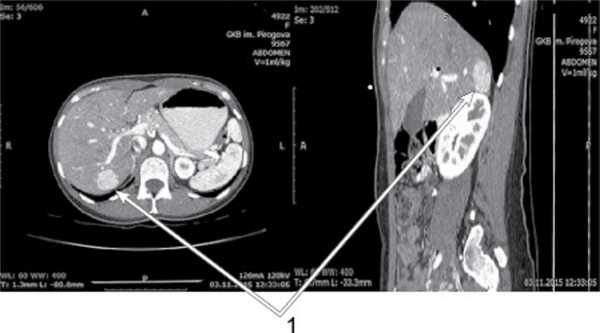

В марте 2018 г. при ультразвуковом исследовании в правой доле печени было верифицировано многокамерное анэхогенное образование 117×89×98 мм с ровными, четкими контурами, неоднородной структуры за счет пристеночных гиперэхогенных включений и взвеси; диаметр воротной вены составлял 11 мм, селезеночной вены — 5 мм, холедоха — 6 мм, внутрипеченочные желчные протоки не были расширены, селезенка — 110×56 мм. Заключение: объемное кистозное образование правой доли печени (эхинококковая киста?). В апреле 2018 г. выполнена магнитно-резонансная томография (МРТ) с контрастным усилением: в правой доле печени имелось многокамерное кистозное образование размером 106×87×97 мм, компримирующее прилежащие отделы паренхимы, несколько деформировавшее ход холедоха, воротной вены, диаметр последних составлял 8 и 12 мм соответственно, а селезеночной вены — 6 мм. Заключение: кистозное обра-зование правой доли печени — наиболее вероятно эхинококковая киста (рис. 1, 2). Рис. 1. МРТ брюшной полости, фронтальный срез: кисты компримируют прилежащую паренхиму печени, деформируют воротную вену. Рис. 2. МРТ брюшной полости, горизонтальный срез: множественные кисты правой доли печени. При иммуноферментном анализе крови иммуноглобулины класса G к антигенам эхинококка однокамерного не обнаружены, в общем анализе крови количество эозинофилов и скорость оседания эритроцитов не превышали норму — эхинококкоз лабораторно не подтвержден.